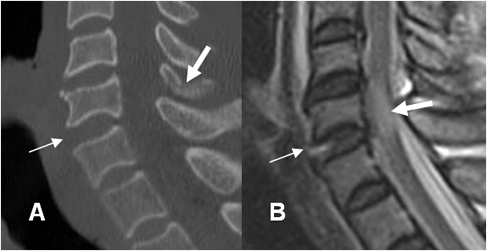

Fig 201 A. Lesión por hiperextensión.

A: TAC reconstrucción lateral. Incremento del espacio intervertebral anterior entre C5 y C6.

Fractura no desplazada en los elementos posteriores. (Flecha gruesa).

B: RM sagital en T2. Ruptura del ligamento intervertebral común anterior. Hiperintensidad del cordón medular, por contusión asociada. (Flecha gruesa).

Fig 201 B. Fractura por hiperextensión.

Rx lateral. Fractura en la parte anterior del cuerpo, con fragmento mas ancho, que alto.